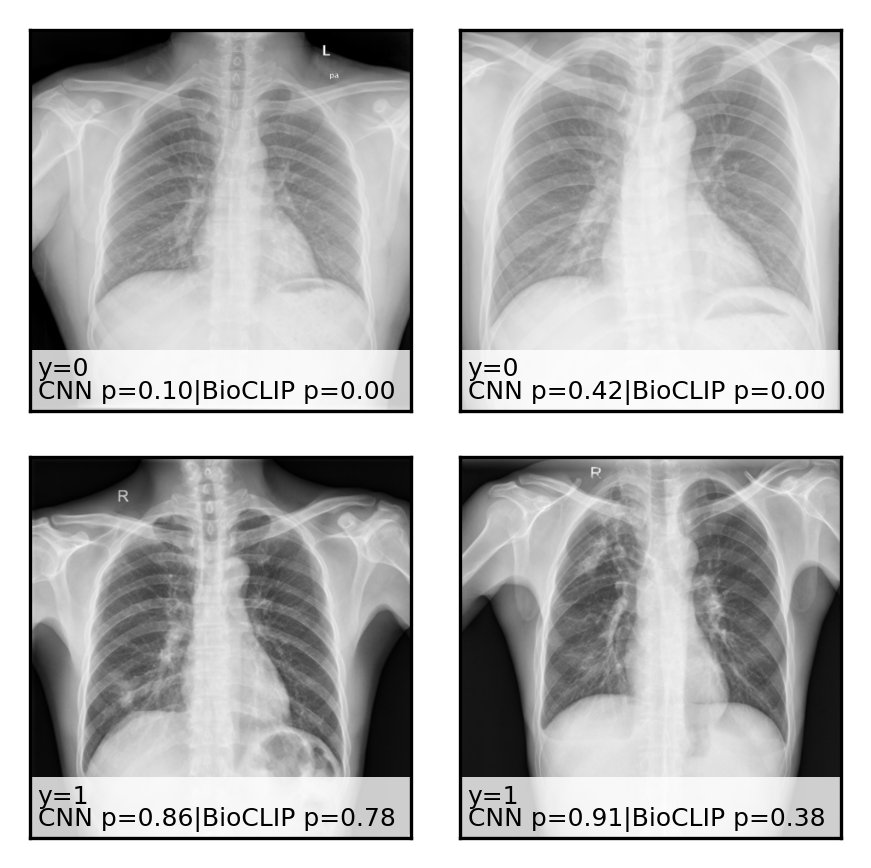

IV-D Qualitative Analysis

To better understand the models’ behaviors, we conduct a qualitative analysis of their predictions.

Figure 1 displays sample images from the PneumoniaMNIST test set. The trained CNN is highly confident in its predictions, with probabilities typically being either 1.00 or 0.00. In contrast, the zero-shot VLM provides more graded probabilities, which helps explain why threshold calibration is so impactful. Figure 2 shows a similar panel for the Shenzhen TB dataset, again illustrating the different probability distributions of the CNN and BiomedCLIP.